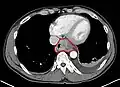

Additional testing is needed to assess how much the cancer has spread (see #Staging, below). Computed tomography (CT) of the chest, abdomen and pelvis can evaluate whether the cancer has spread to adjacent tissues or distant organs (especially liver and lymph nodes). The sensitivity of a CT scan is limited by its ability to detect masses (e.g. enlarged lymph nodes or involved organs) generally larger than 1 cm.[41][42] Positron emission tomography is also used to estimate the extent of the disease and is regarded as more precise than CT alone.[43] Esophageal endoscopic ultrasound can provide staging information regarding the level of tumor invasion, and possible spread to regional lymph nodes.

Contrast CT scan showing an esophageal tumor (axial view)

Contrast CT scan showing an esophageal tumor (coronal view)